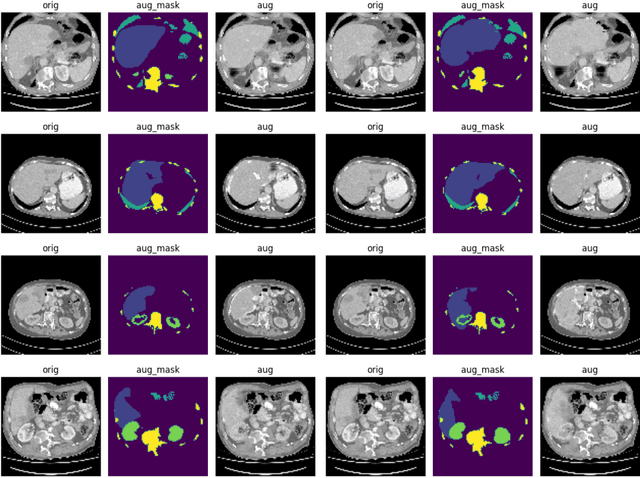

Abstract:Multi-organ segmentation is a widely applied clinical routine and automated organ segmentation tools dramatically improve the pipeline of the radiologists. Recently, deep learning (DL) based segmentation models have shown the capacity to accomplish such a task. However, the training of the segmentation networks requires large amount of data with manual annotations, which is a major concern due to the data scarcity from clinic. Working with limited data is still common for researches on novel imaging modalities. To enhance the effectiveness of DL models trained with limited data, data augmentation (DA) is a crucial regularization technique. Traditional DA (TDA) strategies focus on basic intra-image operations, i.e. generating images with different orientations and intensity distributions. In contrast, the interimage and object-level DA operations are able to create new images from separate individuals. However, such DA strategies are not well explored on the task of multi-organ segmentation. In this paper, we investigated four possible inter-image DA strategies: CutMix, CarveMix, ObjectAug and AnatoMix, on two organ segmentation datasets. The result shows that CutMix, CarveMix and AnatoMix can improve the average dice score by 4.9, 2.0 and 1.9, compared with the state-of-the-art nnUNet without DA strategies. These results can be further improved by adding TDA strategies. It is revealed in our experiments that Cut-Mix is a robust but simple DA strategy to drive up the segmentation performance for multi-organ segmentation, even when CutMix produces intuitively 'wrong' images. Our implementation is publicly available for future benchmarks.

Abstract:Multi-organ segmentation in medical images is a widely researched task and can save much manual efforts of clinicians in daily routines. Automating the organ segmentation process using deep learning (DL) is a promising solution and state-of-the-art segmentation models are achieving promising accuracy. In this work, We proposed a novel data augmentation strategy for increasing the generalizibility of multi-organ segmentation datasets, namely AnatoMix. By object-level matching and manipulation, our method is able to generate new images with correct anatomy, i.e. organ segmentation mask, exponentially increasing the size of the segmentation dataset. Initial experiments have been done to investigate the segmentation performance influenced by our method on a public CT dataset. Our augmentation method can lead to mean dice of 76.1, compared with 74.8 of the baseline method.